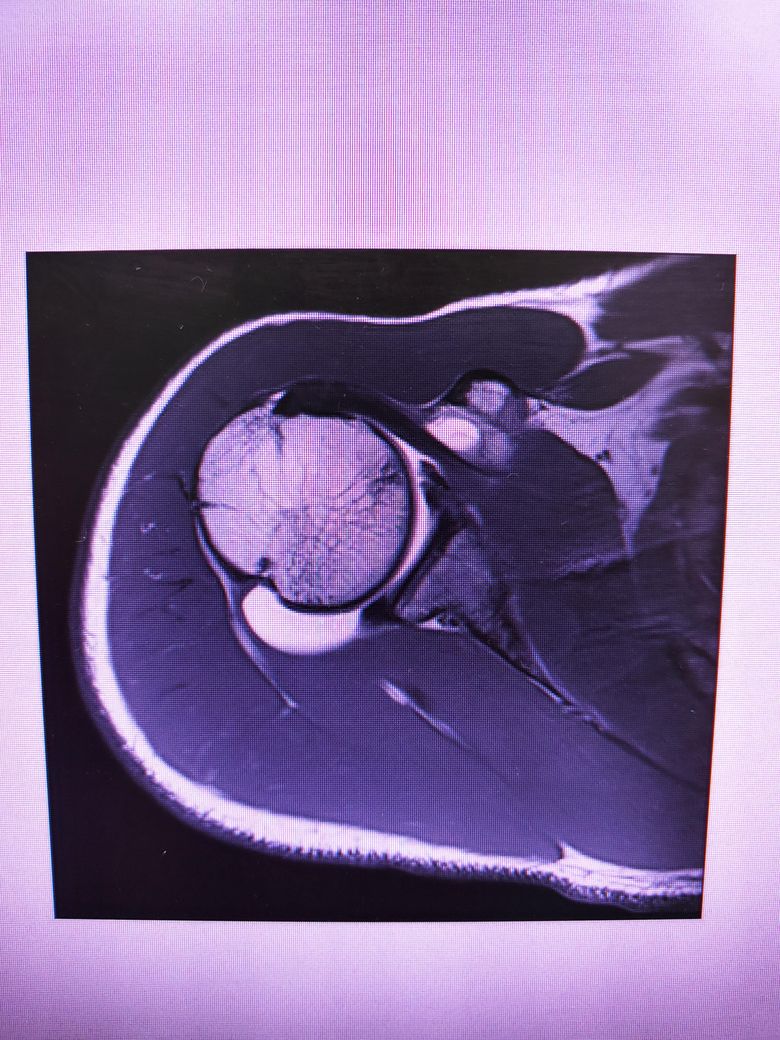

방카르트인지 한번 봐주시겠어요?

어깨를 움직일때 뒤쪽에 깊숙한 통증이있습니다.

염증인거 같긴한데 와순파열은 아닐지 걱정됩니다.

다음 사진에서 방카르트 소견이 있는 건지 봐주실 수 있을까요

• 1번 째 사진

MRI 4컷만 가지고는 방카트 병변을 명확하게 진단하기 어렵습니다.

현재 사진만으로는 방카트로 보이지는 않습니다.